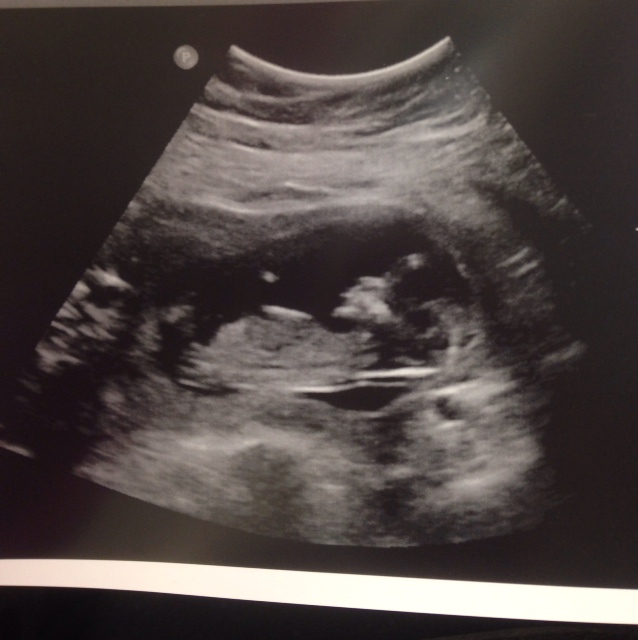

Hi all! We had our NT scan yesterday, and the tech was able to make a guess based on the angle of the dangle! I'd love to hear what you all have to say. I don't know if you can see the actual nub in this picture, but it's the best one I have. Thanks in advance for all your wisdom.

Attachment 17492